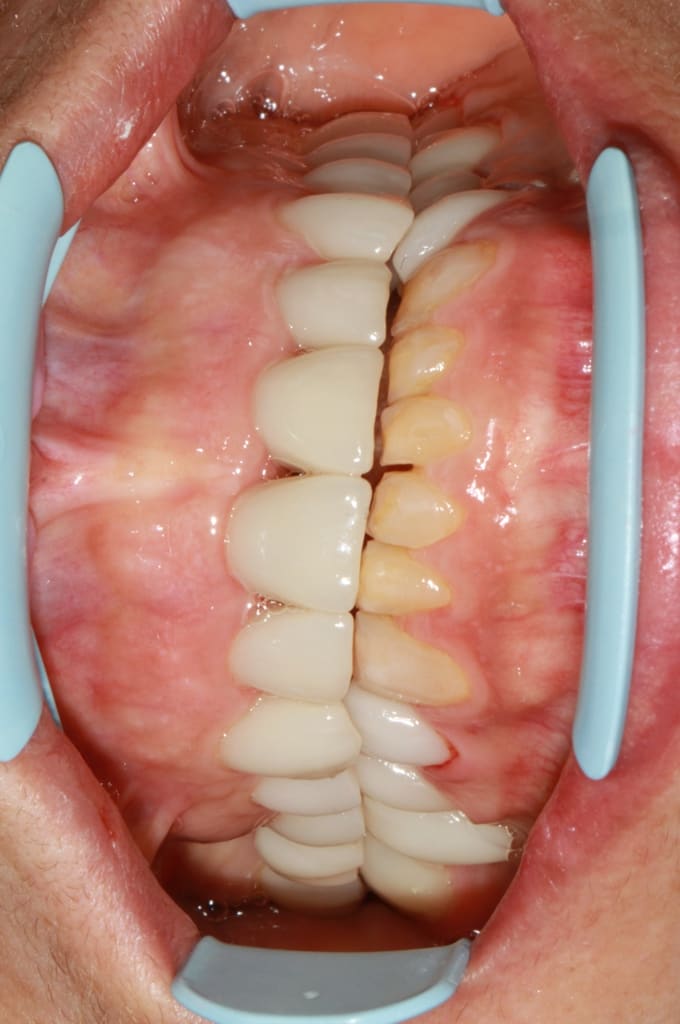

Img 6107 dpg3by - Eugenol

Img 6108 v9ehr3 - Eugenol

Img 6110 b83adw - Eugenol

enlaye

09/02/2018 à 12h32

ayé , je les ai mises .

ah ouiii , mais bouche fermée , ça fait 1 peu cachotteries :-)

j 'ai compris , tu as fais les secteurs post du bas jusqu'aux canines en prov en fonction de ton haut . , et apres tu vas voir ce qui se passe .

bon j'te rassures il ne se passera rien de spécial puisque tes prov de sur-elevation font fonction de gouttierre de relaxation . par contre tes canines vont avoir une forme de talon de santiag .

finalement tu fais par le haut , à la fois l'esthetique et la ( les ) fonction , puis tu adapteras le bas en fonction de la place disponible .